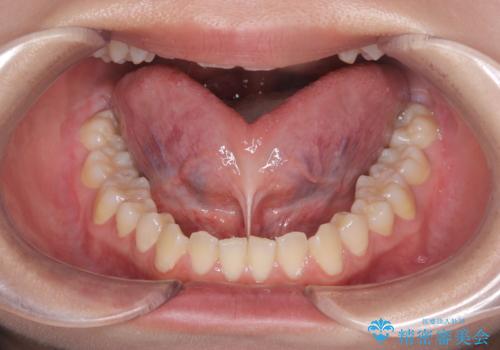

短い舌小帯に舌が引っ張られて舌がハート型になっています。

今まで動いていなかった舌は筋肉が衰えてますので、術後はMFT(舌を動かす訓練)を行うことが大事です。